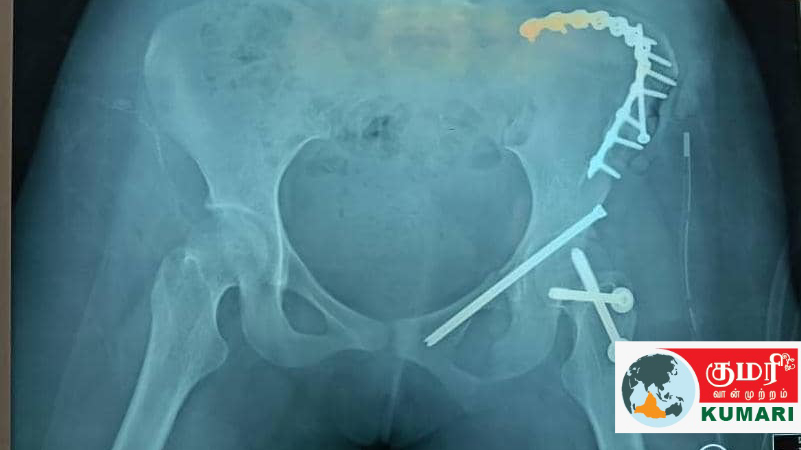

சம்பவத்தன்று சமேதா பயணம் செய்து கொண்டிருந்த மோட்டார் சைக்கிளை, கட்டுப்பாடு இல்லாத வேகத்தில் வந்த யாரோ ஒரு வாகன ஒட்டி, இடித்துவிட்டு நிற்காமல் சென்றுவிட்ட நிலையில், தடுமாறிய சமேதா, பக்கத்தில் இருந்த விளக்குக் கம்பத்தில் மோதி இடுப்பு எலும்பு முறிவுக்கு ஆளானார்.

தவிர இரு கால்களிலும் எலும்பு முறிவு ஏற்பட்டு படுத்த படுக்கையாக தொடர் சிகிச்சை பெற்று வருகின்ற நிலையில், ஆறு பிள்ளைகளுக்கு தந்தையான சரவணா தீர்த்தா, அன்றாடம் மருத்துவமனைக்குச் சென்று மகளை பார்த்துவிட்டு மற்ற பிள்ளைகளின் படிப்பு சம்பந்தமாக பள்ளிக்கும் டியூஷன் மையங்களுக்கும் என அலைந்து கொண்டிருக்கிறார்.

உடைந்த இடுப்பு எலும்புகளை இணைப்பதற்காக இரும்புத் தகடு பொருத்தி ஏற்கெனவே அறுவை சிகிச்சை செய்த இடத்தில் தொற்றும் புண்ணும் ஏற்பட்டிருப்பதால் அறுவை சிகிச்சை செய்த இடத்திலேயே மறு அறுவை சிகிச்சை மேற்கொள்ளப்பட்டது.

வலி மிகுதியால் சமேதா அதிக வேதனைப் பட்டதை அடுத்து அந்த இடத்தை ஆய்வு செய்த சிறப்பு மருத்துவர்கள் தொற்று ஏற்பட்டு இருப்பதை கண்டறிந்ததால் மீண்டும் இந்த அறுவை சிகிச்சை நேற்று மேற்கொள்ளப்பட்டது என்றும் அதேவேளை இரும்புத் தகட்டிற்கு பதிலாக அந்த இடத்தில் மெல்லிய கம்பிகளை இணைக்க முடியுமா என்பது பற்றியும் இந்த அறுவைச் சிகிச்சையின் போது சிறப்பு மருத்துவர் ஆலோசித்ததாகவும் சரவண தீர்த்தா மேலும் சொன்னார்.